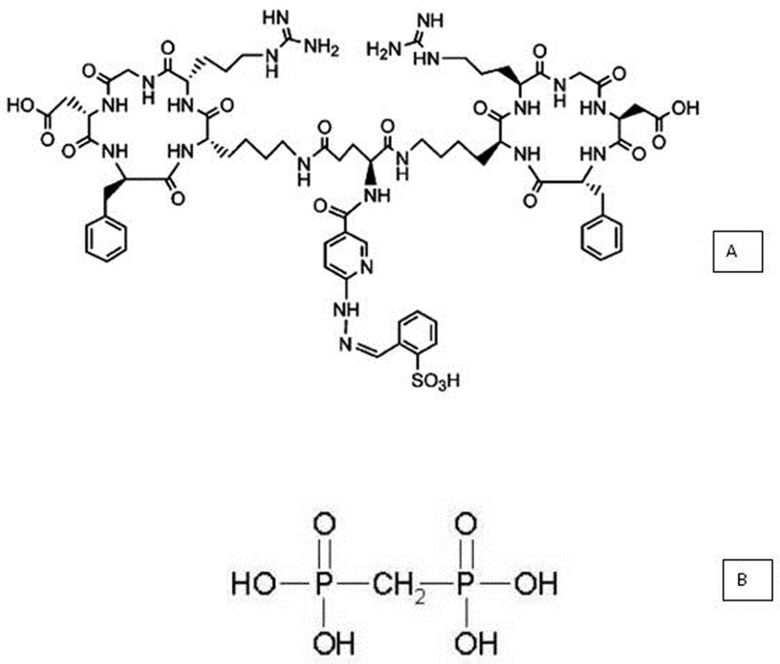

Materials- a.

The cyclic homodimer peptide-conjugated arginine-glycine-aspartic acid and D-phenylalanine-lysine analog, with glutamic acid connecting the dimers [abbreviated (HYNIC-E-[c(RGDfK)2)] (MW 1453.6, peptide purity: 95%), was purchased from CPC Scientific Inc. (Sunnyvale, CA, USA) as lyophilized powder (Figure 1A). The conjugate was dissolved in sterile water at a concentration of 687.94 µM and was stored at -20°C.

- b.

A lyophilized medronic acid kit consisting of 10 mg of medronic acid (Figure 1B), 1.2 mg of dehydrated stannous chloride, and 2 mg of paraminobenzoic acid (produced in house) was used (Radiopharmacy Center, Institute of Energy and Nuclear Research/National Commission of Nuclear Energy-IPEN/CNEN, São Paulo, SP, Brazil).